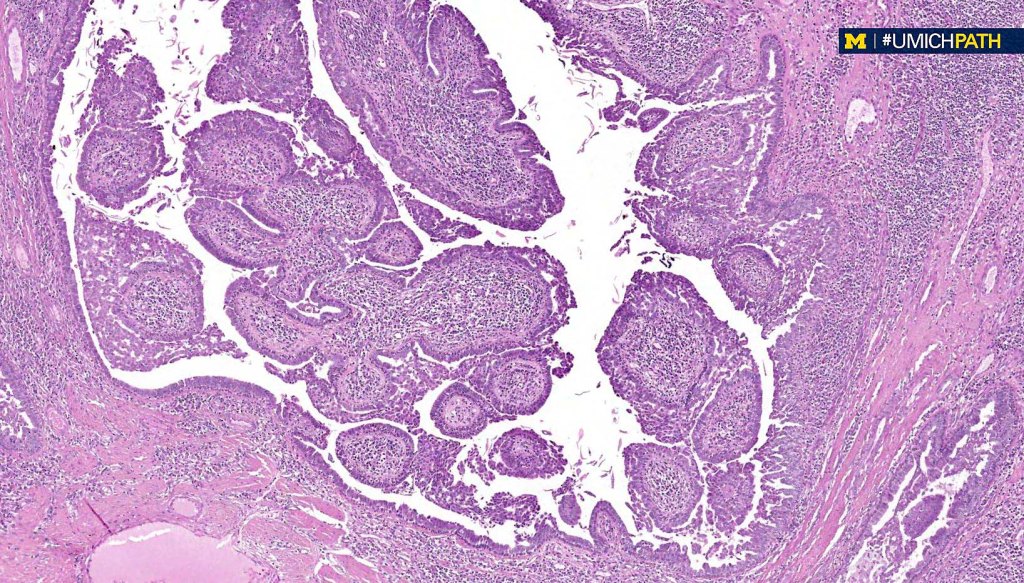

•Scanning magnification shows an exophytic tumor or an epidermal invagination enclosing epithelial covered papillae with a fibrovascular core

•Glands are present at the base of the lesion

•At the edges, the squamous epithelium is in continuity with the glandular one

•The epithelium consists of outer myoepithelial cells supporting an inner layer of columnar cells with abundant eosinophilic cytoplasm showing decapitation secretion

•Dense plasma cell infiltrate